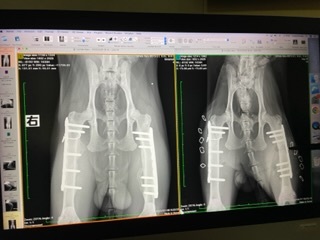

病院にてレントゲン撮影

※文末にレントゲン写真を2枚掲載しています。苦手な方は避けてください。

7/8 病院でハルくんのレントゲンを撮影してきました。

1ヶ月半ぶりの撮影ですが、無事に骨が固定されて、両脚の筋肉も大きく発達していました。獣医さんにも「制限なく走り回って大丈夫ですよ」と言われました。

念の為、半年後にプレートのズレがないか確認しますが、ひと安心です。両脚骨折で這う事しかできなかったハルくんがここまで回復できてびっくりです。良かった!

※レントゲン写真

(左が7月撮影:筋肉が盛り上がり、プレートが骨と筋肉によりしっかり固定されている折れた骨も治っている)